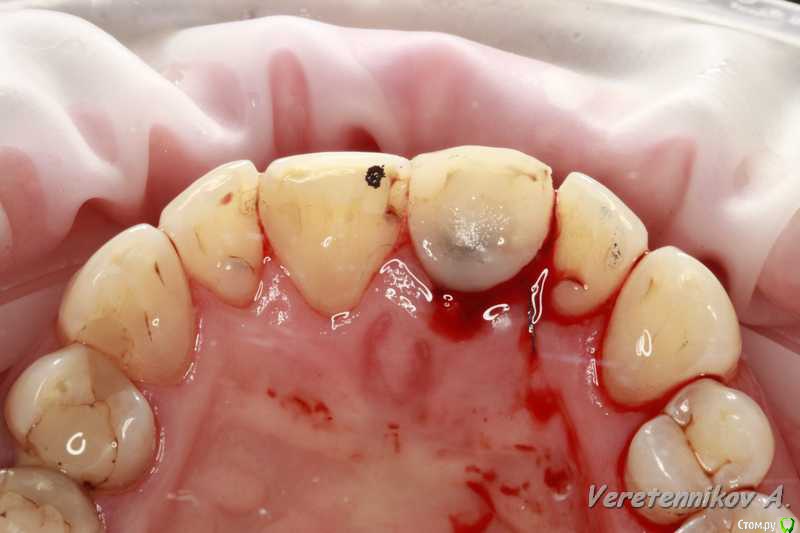

Популярный пост an_ver Опубликовано 15 января, 2016 Популярный пост Поделиться Опубликовано 15 января, 2016 11,жил долго и счастливо..но тут Новый год(((, скол ниже уровня ЦЭС на 3 мм...от экструзии отказалась.Из своего зуба сколхозил шаблон,чтоб наверняка. Удалил,кюретаж,вестибулярка целая, SPI 4.2*13 мм,с бугра ССТ,на всякий)),в щели Апатос,врем.абатмент,врем.коронка из своего зуба. 1ч.20мин.)) 27 Ссылка на комментарий